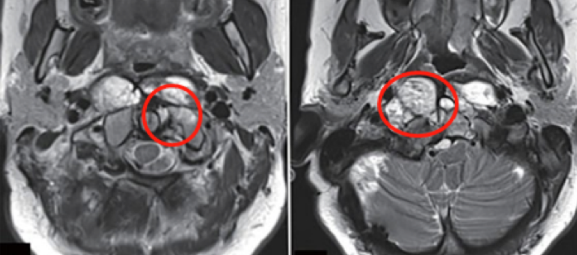

一步的手術比較成功,術后沒有新的神經功能缺損、顱神經功能障礙或腦脊液滲漏。二次手術基本上達到全切,椎弓根僅可見少量殘留。在接下來的五個多月里,我還接受了Froelich教授建議的質子治療(總計70.2 Gy)。目前,距離上次治療完已經將近3年,通過隨訪,并無發(fā)現(xiàn)有腫瘤進展跡象。

法國脊索瘤手術案例圖片

法國脊索瘤手術案例